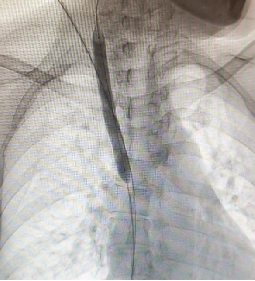

肾脏内科龚蓉主任带领团队回顾病史发现,李阿姨已经使用原半永久血透导管进行血液透析3年有余,近半年透析不时会出现导管流量下降、透析效率不达标等情况,考虑存在透析导管所致中心静脉病变,传统方式重新置管风险高、难度大,肾内科林新强主治医生与放射介入科刘武军主任联合为患者制定了个性化的手术方案,在数字减影血管造影(DSA)引导下见患者的右侧颈总静脉与右锁骨下静脉汇合部及上腔静脉起始部狭窄,使用10mm球囊扩张后狭窄病变明显改善,血流恢复通畅,并顺利置入新的半永久血透导管。

(球囊扩张血管狭窄部位)